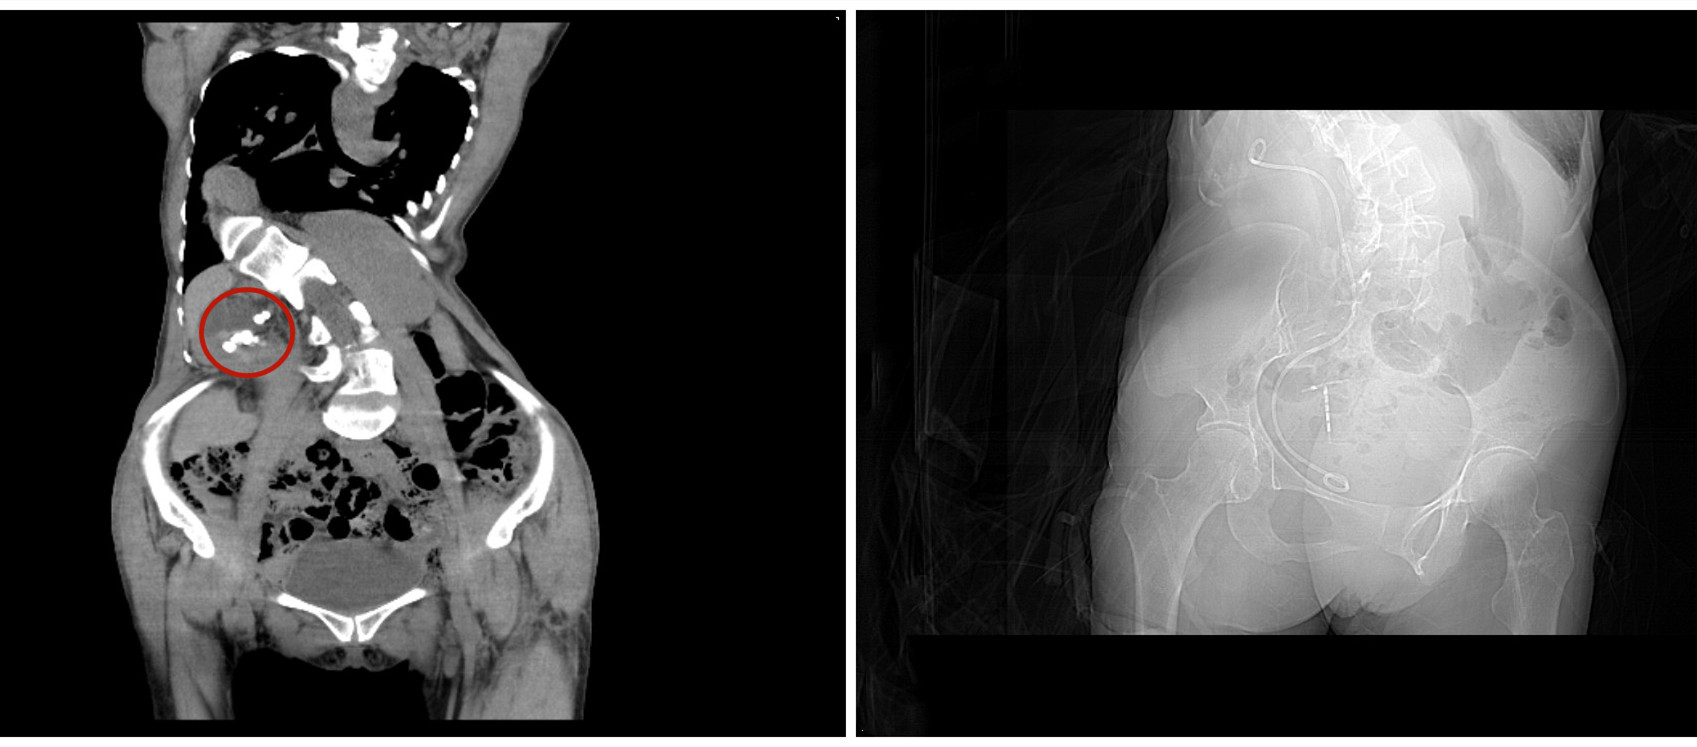

术中发现,张大姐脊柱严重畸形,双侧肾脏和变形的脊柱结合婉如“太极八卦阵”扭曲在体内,而肾脏和输尿管受到脊柱挤压已严重错位,上尿路的解剖结构也明显改变,这些都无疑加大了手术难度。手术需将一根纤细的穿刺针直接从腰背部进入肾脏,建立取石通道,置入肾镜,使用激光击碎结石并取出。但因其腰部躯体内收,使胸廓与骨盆夹角变小,同时手术空间明显狭窄,且被临近器官特别是肠管覆盖,极大的增加了穿刺难度和风险。团队面对这“位置不正常”的肾脏,依靠娴熟的手术能力和团队合作,终于将肾内的结石清除干净,其中最大的约有樱桃大小。